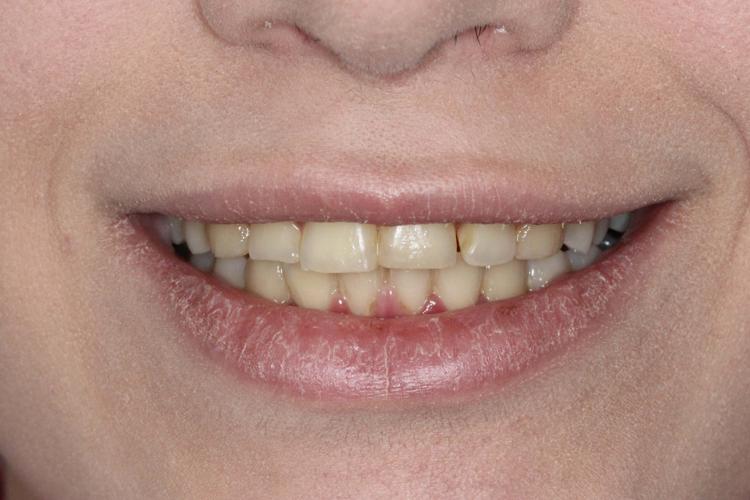

نتایج درخشان قبل و بعد از ارتودنسی در ستاره شرق

نتایج درمانهای ارتودنسی در کلینیک ستاره شرق